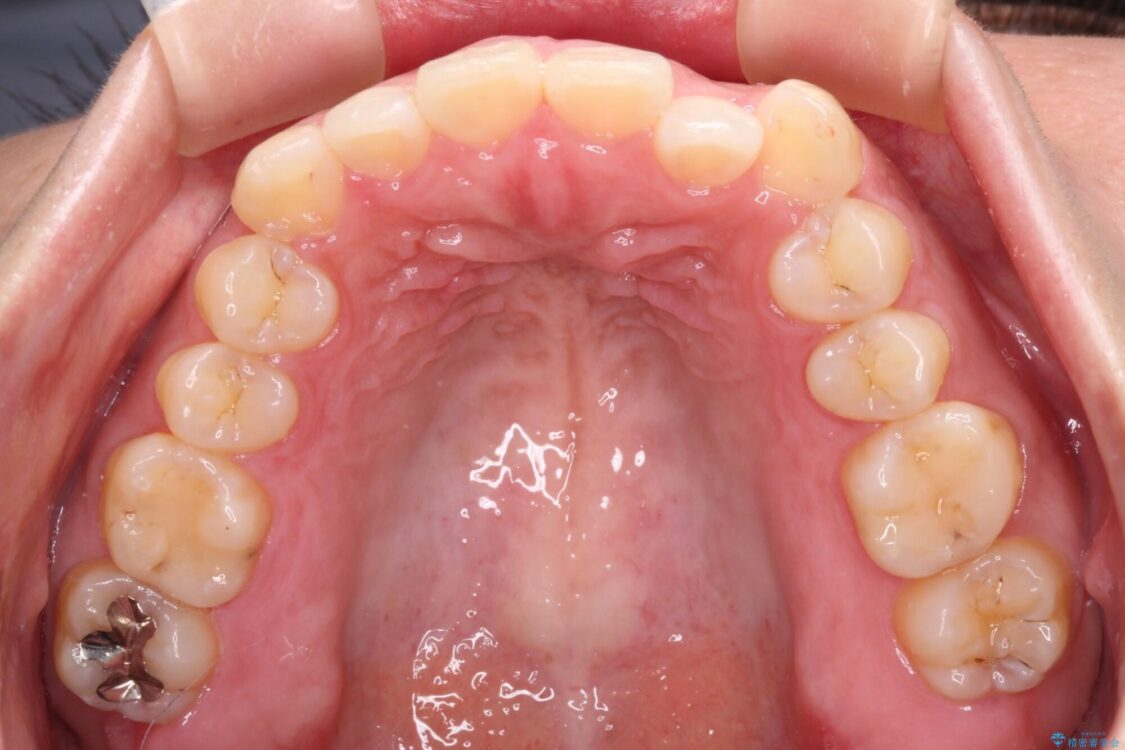

前歯の叢生と八重歯を気にして来院された患者様です。

治療前

• 【モニター】カリエール・ディスタライザーを併用した八重歯のインビザライン矯正 治療前画像